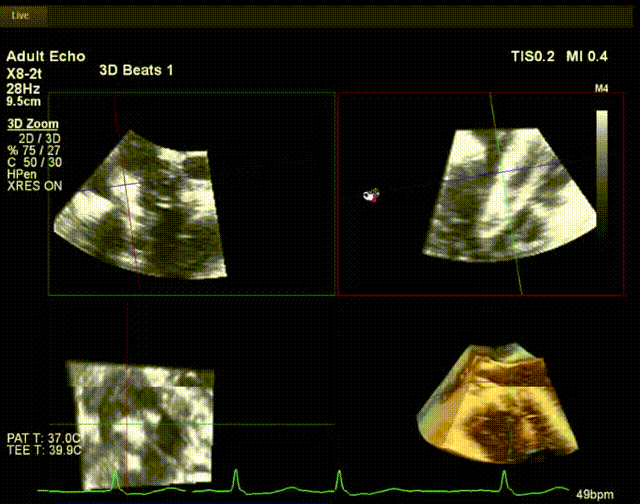

術中超聲

手術在全麻狀態(tài)下開展,此次手術采用經(jīng)頸靜脈入路的方式。在TEE及DSA雙重引導下,術者調(diào)整輸送器頭端角度使得其與三尖瓣瓣環(huán)平面垂直。在輸送器進入右心室后釋放室間隔錨定裝置,而后釋放瓣葉夾持件(2個耳片結構)成垂直狀態(tài)。在TEE及DSA確定夾持件固定至三尖瓣葉根部且位于右室側后釋放人工瓣心房側盤片。隨后調(diào)整瓣膜同軸性以及室間隔錨定件位置(貼合室間隔),進而釋放室間隔錨定裝置,并再次確認瓣膜位置、穩(wěn)定性及同軸性,解離人工瓣膜與輸送器間連接,并撤出輸送器,完成了LuX-Valve Plus人工三尖瓣瓣膜的植入。

陸方林教授通過遠程線上帶教的方式,與林逸賢教授團隊共同完成了此次LuX-Valve Plus人工瓣膜的首例植入。術后食道超聲提示三尖瓣反流完全消失,無瓣周漏,且LuX-Valve Plus人工瓣膜的兩個夾持鍵成功抓取瓣葉,錨定牢固,人工瓣膜穩(wěn)定性良好。